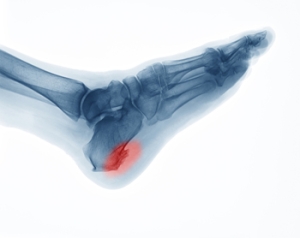

What is a Heel Spur and How Can it be Treated?

A heel spur may occur when a calcium deposit develops between the arch of the foot and the heel. A common symptom of a heel spur often includes a sharp, intense pain when standing up in the morning. Additional signs you may have a heel spur may consist of an ache, inflammation or swelling in the heel, heat radiating from the affected area, and a noticeable protrusion under the heel. Factors that increase the risk of obtaining a heel spur can include being involved in athletic activities, experiencing trauma to the heel, general aging, and wearing improper footwear. Getting proper rest, and using custom made orthotics may help to alleviate any pain or pressure that exists as a result of a heel spur. If you would like additional information and advice for an effective treatment regime, we recommend that you consult with a podiatrist.

Heel spurs are formed by calcium deposits on the back of the foot where the heel is. This can also be caused by small fragments of bone breaking off one section of the foot, attaching onto the back of the foot. Heel spurs can also be bone growth on the back of the foot and may grow in the direction of the arch of the foot.

Older individuals usually suffer from heel spurs and pain sometimes intensifies with age. One of the main condition's spurs are related to is plantar fasciitis.

Pain

The pain associated with spurs is often because of weight placed on the feet. When someone is walking, their entire weight is concentrated on the feet. Bone spurs then have the tendency to affect other bones and tissues around the foot. As the pain continues, the feet will become tender and sensitive over time.

How to Treat Heel Spurs

Heel spurs are calcium deposits that cause bone protrusions on the heel bone. Heel spurs are usually associated with plantar fasciitis, which occurs when the plantar fasciitis in the foot becomes inflamed. Typically, heel spurs don’t cause any symptoms. However, they can produce chronic or intermittent heel pain. Those who have had the condition often describe the irritation as a stabbing pain.

The pain associated with heel spurs often decreases the more you walk. However, a recurrence of pain after an extended period of rest or walking is likely to occur with this condition. Those with severe heel spur pain may opt to go the surgical route for treatment. However, more than 90% of those with the condition get better without surgical treatment. If you have a heel spur and want to know if surgery is right for you, you should go to your podiatrist and he or she will be able to conduct a pre-surgical test or exam to determine if you are an optimal candidate for surgery.